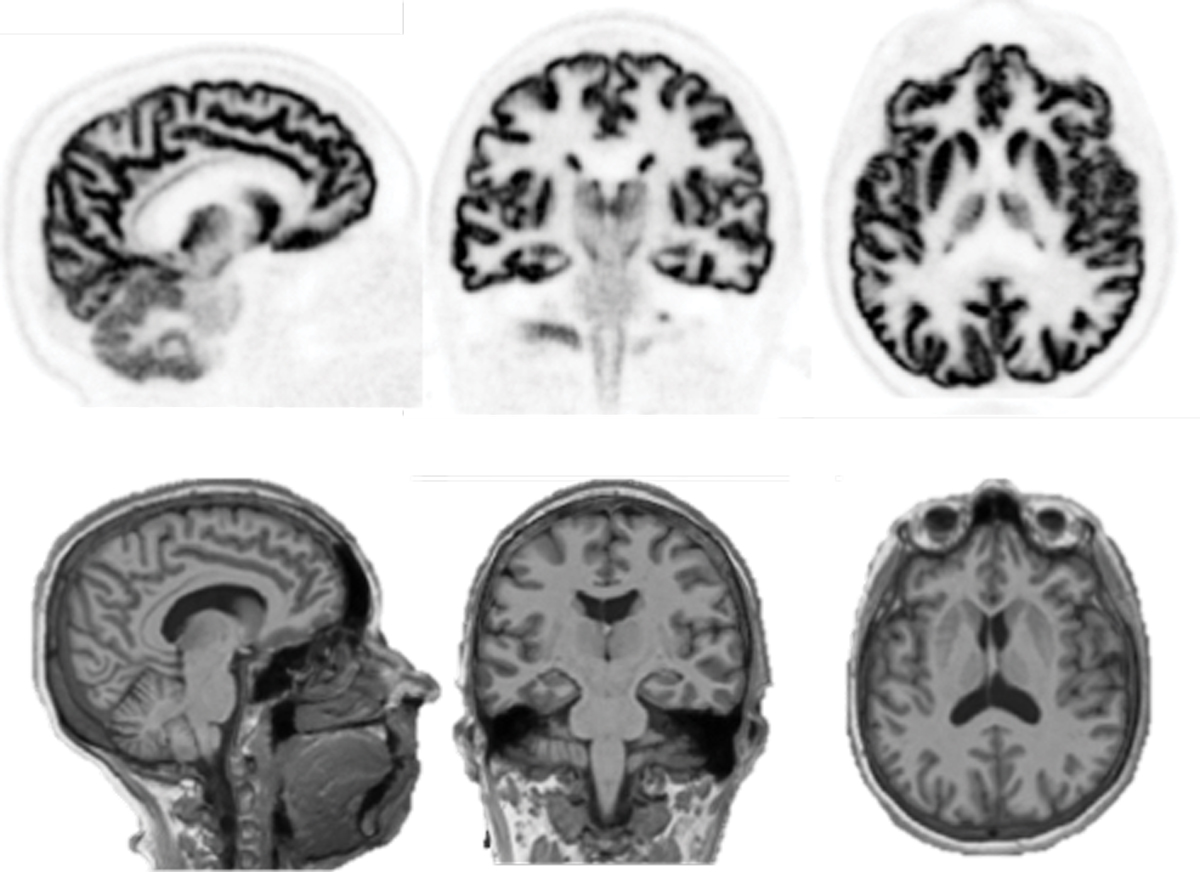

Figure 5.

PTO.v78.i9.28_1.f5.jpg

Image slices of the brain of a healthy control participant (top row), acquired 60–90 minutes after injection of a radiolabeled synaptic density marker. The images were made using a new dedicated human-brain PET imager, NeuroEXPLORER. Matching MRI anatomical images were also captured (bottom row). The ultrahigh resolution and sensitivity of the NeuroEXPLORER provide exquisite delineation of the folds of the brain’s cerebral cortex and structures deeper in the brain. (Image courtesy of Richard Carson on behalf of the NeuroEXPLORER consortium.)

New brain-only imaging units are being developed with an unprecedented isotropic resolution that approaches 2 mm3, which is comparable to but not quite as high as that of MRI. PET brain images, like those shown in figure 5, reveal the biochemical distribution of radiopharmaceuticals that enables the detailed probing of, for example, specific neuroreceptors, amyloid deposition in Alzheimer’s disease, and even synaptic densities.